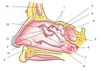

1

Frontal sinus

2

Nasal bone

3

Perpendicular plate of ethmoid bone

4

Septal cartilage

5

Vomer

6

Alveolar margin of maxilla

7

Palatine process of maxilla

8

Palatine bone

9

Sphenoid sinus

11

Sella turcica

12

Cribriform plate (of ethmoid bone)

13

Crista galli (of ethmoid bone)

A

Frontal sinus

B

Superior nasal concha (of ethmoid bone)

C

Middle nasal concha (of ethmoid bone)

D

Inferior nasal concha

E

Nasal bone

F

Maxillary bone

G

Palatine bone (perpendicular plate)

H

Pterygoid process (of sphenoid bone)

I

Sphenoid sinus (of sphenoid bone)

J

Superior, middle, and inferior meatus